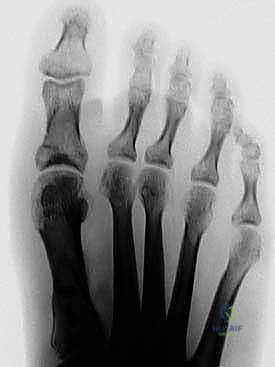

في حالة إبهام القدم الأروح، ينحرف عظم المشط الأول (First Metatarsal) نحو الداخل (نحو القدم الأخرى)، بينما ينحرف إصبع القدم الكبير نفسه نحو الخارج (نحو الأصابع الأخرى). هذا الانحراف المزدوج يخلق الزاوية البارزة التي نراها كـ "ورم". مع مرور الوقت، تتغير أوتار وأربطة القدم، مما يثبت التشوه ويجعله أسوأ.

هذا الخلل الميكانيكي يؤدي إلى خروج عظام السمسمانية (Sesamoid bones) - وهي عظام صغيرة أسفل المفصل تعمل كبكرات للأوتار - من مسارها الطبيعي، مما يسبب تآكلاً للغضاريف وألماً مبرحاً. جراحة ماو تهدف إلى إعادة كل هذه المكونات إلى مسارها التشريحي الصحيح.

بناءً على هذه الزوايا، يتم تصنيف الحالة إلى خفيفة، متوسطة، أو شديدة. جراحة (ماو) تُخصص عادة للحالات المتوسطة إلى الشديدة التي تتطلب تصحيحاً كبيراً ومستقراً.